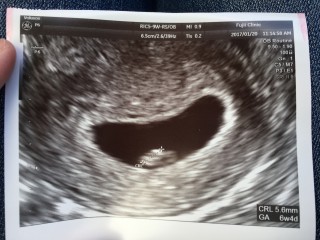

初めての妊娠。 エコー写真を見た時ホントに自分のお腹の中にいるのかなと実感が湧かなかったけど6週4日目でポツンっていて実感が湧いた。血が出たりしてたのですがちゃんと元気に育ってました♪愛するベビー!

6w4d6mm 少量の出血があったり下腹部痛があったけど、異常なしで安心した!これからもすくすく育ってね